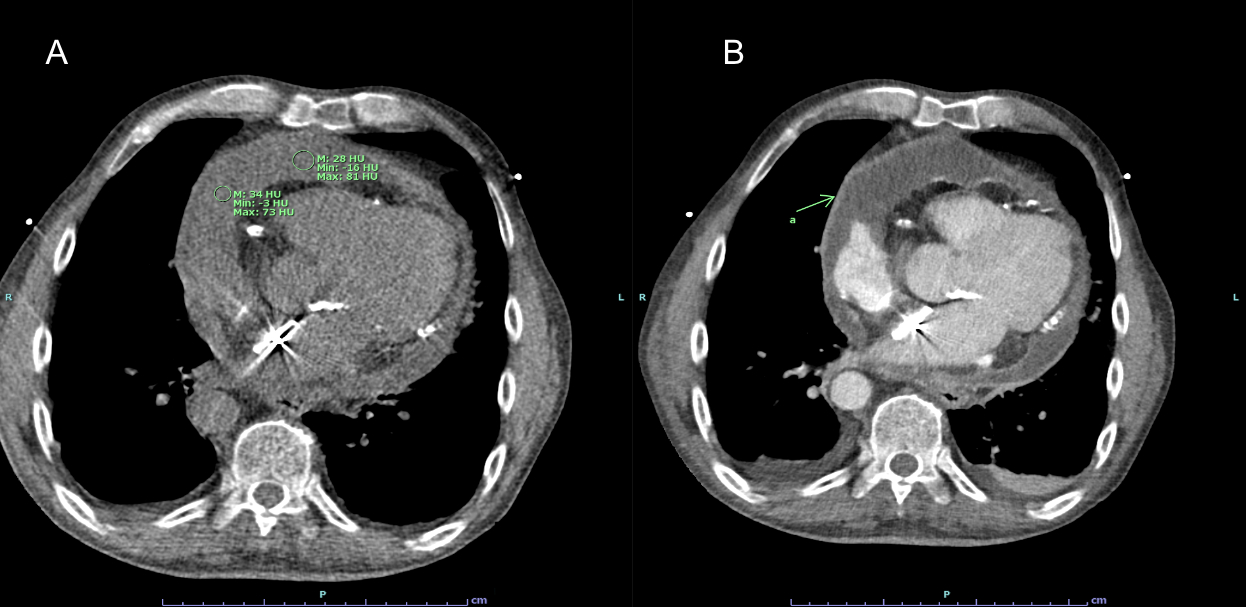

Case Summary: A 65-year-old male with a history of stroke, PFO closure with a 35-mm Amplatzer septal occluder, and deep vein thrombosis on apixaban presented with chest pain and dyspnea. CT imaging showed a large pericardial effusion with early tamponade. Pericardiocentesis drained 1.4 liters of hemorrhagic fluid— fluid analysis indicated inflammatory etiology. The drain was removed after three days, but effusion recurred within 48 hours.

Decision-making: A transesophageal echocardiogram (TEE) was attempted due to suspected device erosion, but it was aborted due to severe cervical kyphosis. Cardiac CT revealed multi-pocketed hemopericardium, clots, thickened pericardium and aortic root edema, with the PFO closure device well-positioned. Limited sternotomy with adhesiolysis, fluid drainage, and pericardiectomy excluded erosion, confirmed an intact aorta and intracardiac device, and treated pericarditis. Fluid analysis, inconclusive for other causes, attributed the effusion to chronic pericarditis.

Discussion: Cardiac CT was pivotal in diagnosing recurrent hemorrhagic effusion and evaluating PFO device position when TEE was infeasible. It detailed effusion extent and pericardial inflammation, guiding surgical planning. Pericardiectomy confirmed device integrity, ruled out erosion—a serious complication causing bleeding or fistulas—and prevented effusion recurrence. This case highlights CT’s diagnostic precision and surgery’s role in managing chronic pericarditis and device-related risks.